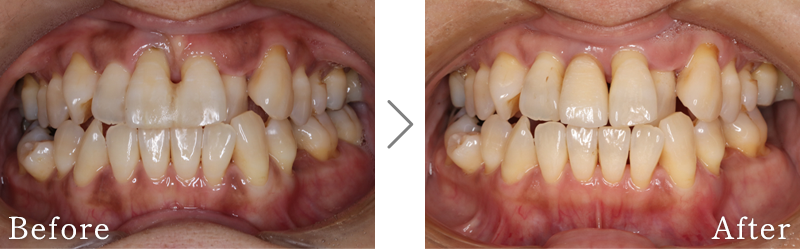

CASE1

主訴 入れ歯も合わず、しっかりと噛んで食事ができないとのことで来院されました。

治療法 上下ともにALL-ON-6と呼ばれる最少本数のインプラントで全ての歯を回復する治療を行なっています。歯の部分は全てセラミックで作成されています。

治療期間 5ヶ月

費用 CT:16,500円(税込)

+ 静脈内鎮静法:77,000円(税込)

+ ALL-ON-6×2:5,500,000円(税込)

合計:5,593,500円(税込)

副作用

• 歯周病に感染・発症し重度に進行するとインプラントが抜けてしまうことがあります。

• 手術後は数日間腫れが出る場合があります。